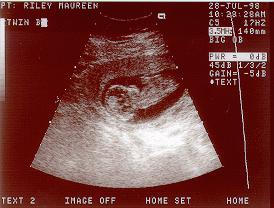

July 28, 1998

12 Weeks, 5 days

Twin "B"

Well, this is "Boris" showing "his" profile. We had a very good visit today. Lots of activity. I think when the ultra sound first started "Boris" and "Abigail" were have a fist fight, or maybe it was kick-boxing. Lots of activity with the arms and the legs.